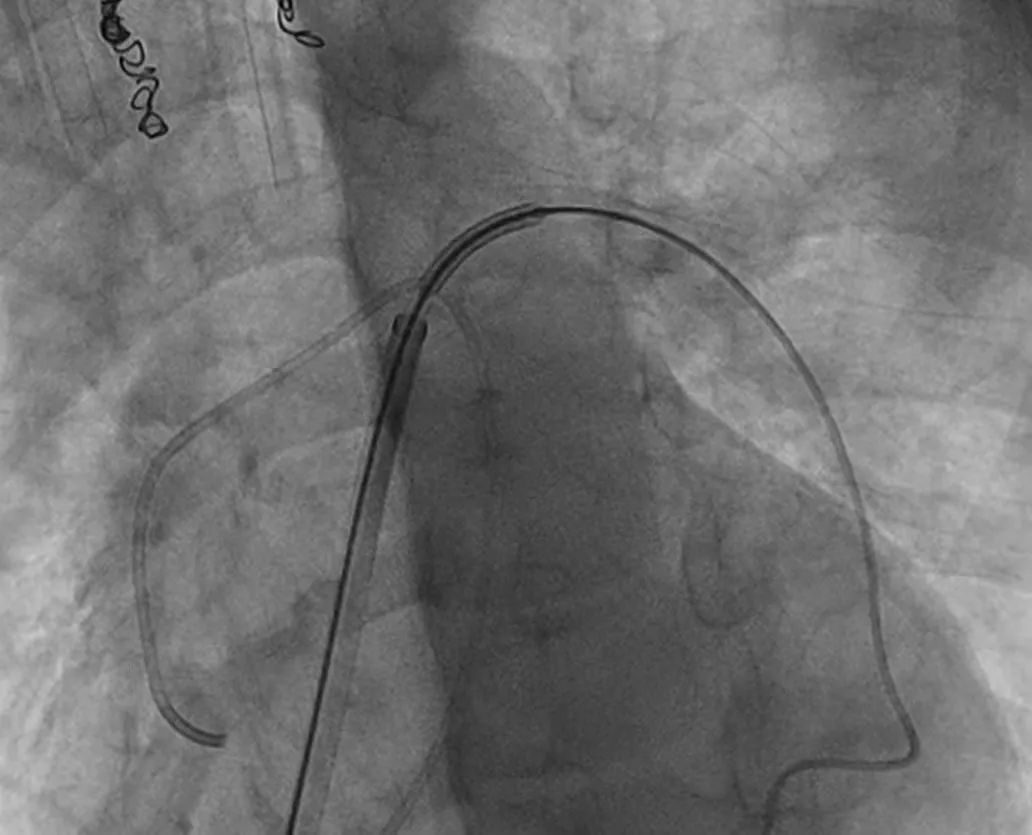

手术在全麻下进行。范太兵教授、宋书波博士等专家精准操作,通过导管建立的生命通道,小心翼翼将可降解铁基支架置入狭窄的左肺动脉处后。

精确定位、释放后,通过造影发现,患儿肺动脉狭窄得到解决,右心室压力显著降低,手术获得成功。

支架扩张前